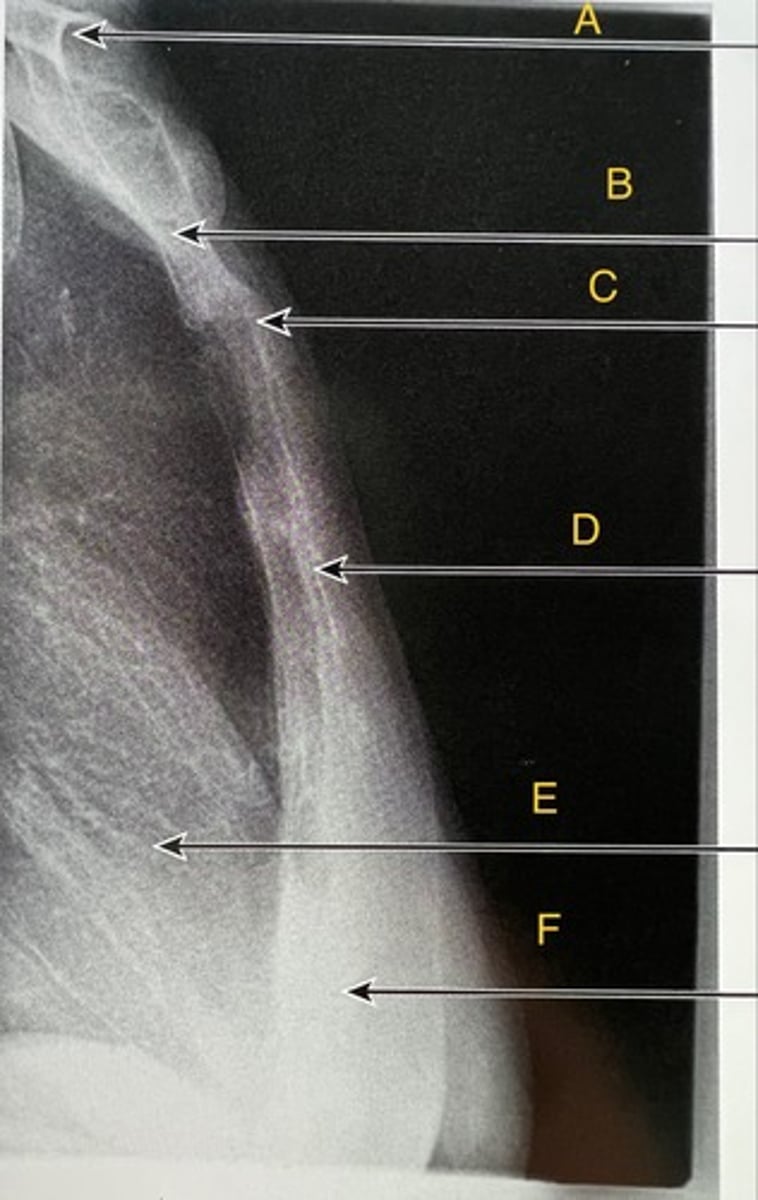

L2 Transverse process

A.

L3 Pedicle

B.

L3 pars interarticularis

C.

L3 inferior articular process

D.

L4 Superior articular process

E.

L3-4 zygapophyseal joint

F.

Oblique lumbar

What position?